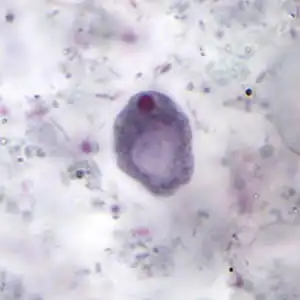

The cysts are 8–10 micrometres in diameter, with a thick wall and a large glycogen vacuole that stains darkly with iodine. Usually harmless, it may cause amebiasis in immunologically compromised individuals.

[5][6] As the second form of I. butschlii, cysts have an oval shaped- single nucleus with a prominent nuclear endosome. This form is also large, single, glycogen-filled vacuole called iodinophilous vacuole (glycogen stains with iodine). Cysts are the infective stage of I. buetschlii. Unlike trophozoites, cysts are often found in formed stools.[4]